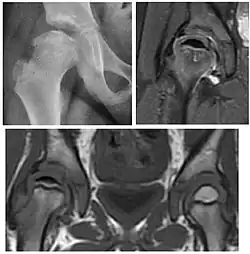

Plain radiography allows us to categorize the hip as normal or dysplastic or with impingement signs (pincer, cam, or a combination of both). Besides these, pathologic processes like osteoarthritis, inflammatory diseases, infection, or tumors can also be identified (Figure 1).[1]

Figure 1.

-

Radiography in normal hip -

X-ray in pincer impingement type of hip dysplasia -

X-ray of cam -

Hip in osteoarthritis -

Septic arthritis

X-ray in pediatrics